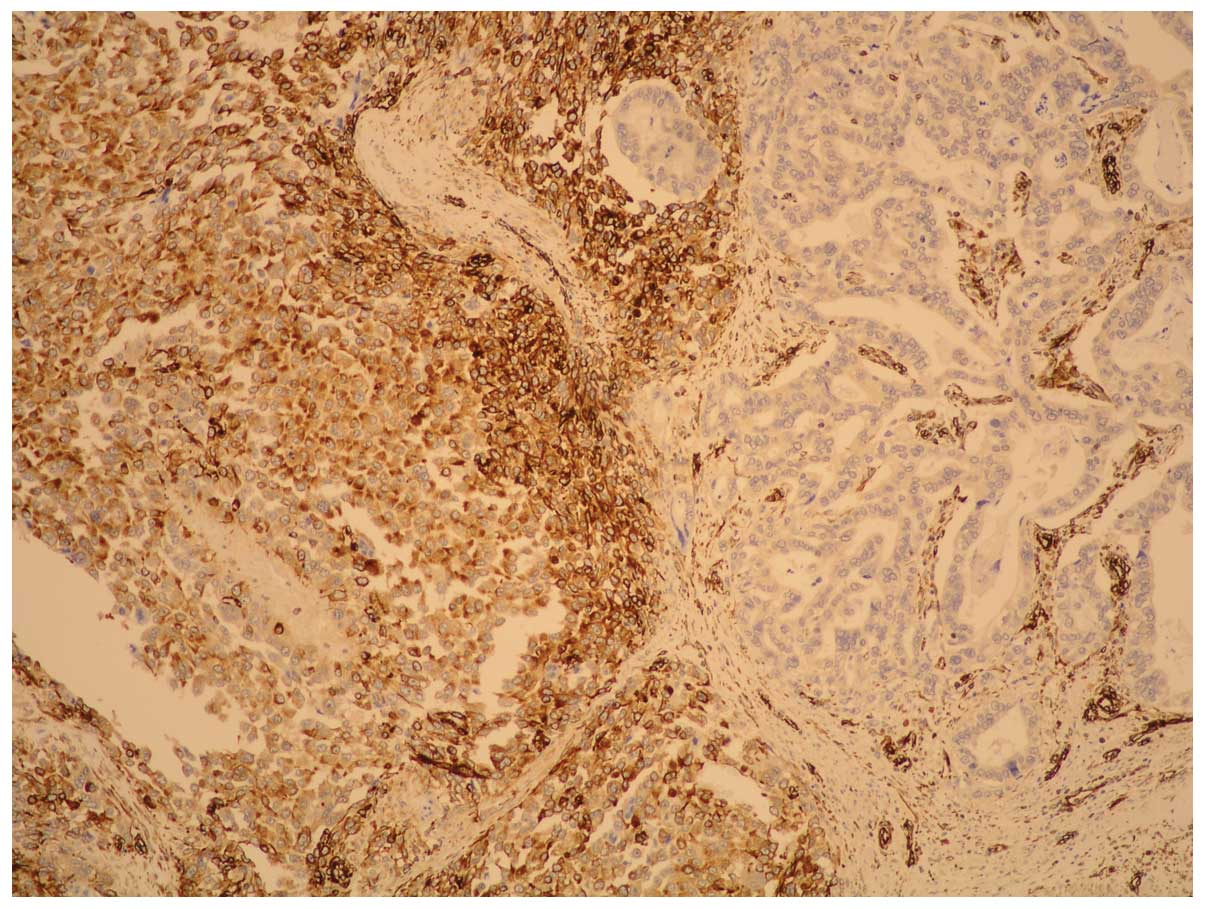

The carcinoma component exhibited a positive

reaction to pan-cytokeratin whereas fusiform cells showed positive

reactions to vimentin: HHF35; CD56; EMA (weak); desmin (singular

component) and negative reactions to cytokeratin, actine,

caldesmon, CD-34, S-100 and cromogranin; synaptophysin, CD-57 and

c-kit. These immunohistochemical findings led to a diagnosis of

gastric carcinosarcoma (Figs. 4 and

5).